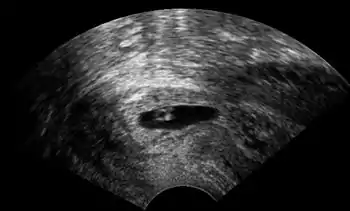

Ultrasonography of a cervical pregnancy